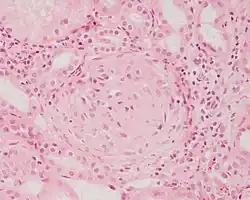

Crescentic glomerulonephritis induced by infective endocarditis on PAS staining and immunofluorescence. PAS staining (left) demonstrated circumferential and cellular crescent formation with interstitial nephritis. Immunofluorescence (right) demonstrated C3 positive staining in mesangial area.

Photomicrograph of renal biopsy showing crescent formation and tuft narrowing. Periodic acid silver methenamine stain.

Rapidly progressive glomerulonephritis, also known as crescentic GN, is characterised by a rapid, progressive deterioration in kidney function. People with rapidly progressive glomerulonephritis may present with a nephritic syndrome. In management, steroid therapy is sometimes used, although the prognosis remains poor.[9] Three main subtypes are recognised:[4]: 557–558

Histopathologically, the majority of glomeruli present "crescents". Formation of crescents is initiated by passage of fibrin into the Bowman space as a result of increased permeability of glomerular basement membrane. Fibrin stimulates the proliferation of endothelial cells of Bowman capsule, and an influx of monocytes. Rapid growing and fibrosis of crescents compresses the capillary loops and decreases the Bowman space, which leads to kidney failure within weeks or months.